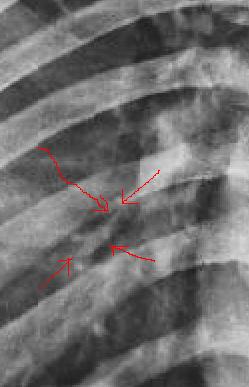

肺纹理吧。

是吗,不太像

光看片是很难看出来的,只有结合刀口处啦。要我看我就看不出来。

兄弟 说句实话  你告诉结果给我  我看的还是不怎么像。。。

刀法不只是好,简直堪称绝妙,若非有透视,我绝认为是肺纹.

同志们!老师们!这个病例的确太难了,真的很像肺纹理。我第一次还下正常报告,幸运还没发出去啊!透视了才下骨折。

这绝对是骨折!